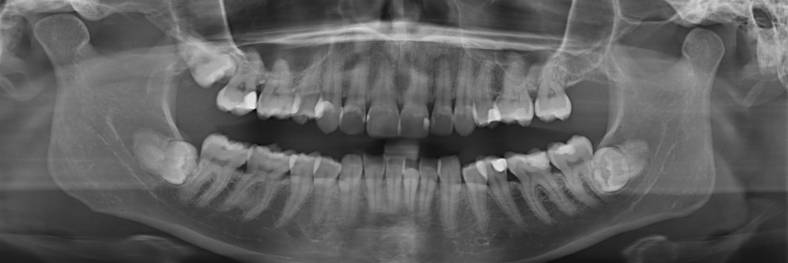

Die operative Entfernung von Weisheitszähnen gehört zu den häufigsten ambulanten dentoalveolären Eingriffen. Über 80% der unteren Weisheitszähne sind verlagert. Eine Indikation zur Entfernung verlagerter, nicht oder nur teilweise durchgebrochener Weisheitszähne unter stationären Bedingungen besteht nur bei gerinnungsgehemmten, gerinnungsgestörten, geistig retardierten oder multimorbiden Patienten.

Medizinische Gründe für die operative Entfernung verlagerter Weisheitszähne ergeben sich aus wiederholten Entzündungen der bedeckenden Schleimhäute (Dentitio difficilis), Karies an benachbarten Zähnen oder der Bildung von follikullären Zysten. Weitere Indikationen sind teilretinierte Weisheitszähne im Spaltbreich bei Unterkieferfrakturen, bei Verdacht auf eine Fokusursache im Kieferbereich oder einer geplanten Strahlen- oder Chemotherapie. Prophylaktische kieferorthopädische Indikationen können ein ausgeprägter Platzmangel im Bereich der Kiefer oder die Prophylaxe eines Engstandes der Zähne sein. Speziell bei prophylaktischen Indikationen sollte eine sorgfältige Kosten-Nutzen- bzw. Risiko-Nutzen-Analyse erfolgen.

Obwohl die Komplikationsrate bei oder nach operativer Weisheitszahnentfernung gering ist, muss auf die Möglichkeit von Sensibilitätsstörungen im Unterkiefer, Wundheilungsstörungen, Eröffnung der Kieferhöhle im Oberkiefer oder Unterkieferfrakturen hingewiesen werden.

Durch die Anfertigung eines präoperativen DVT (3D-Röntgendiagnostik) kann in speziellen Fällen das Risiko einer Nervschädigung mit der Folge eines Sensibilitätsverlustes im Rahmen der operativen Entfernung von Weisheitszähnen im Unterkiefer signifikant reduziert werden.